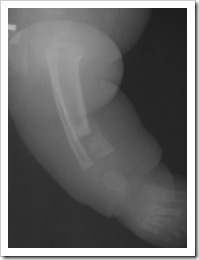

- Typ I – zagięcie przednio-boczne z prawidłowym kanałem szpikowym, prognoza dobra, może nigdy nie dojść do złamania

- Typ II - (sklerotyczny) – zagięcie przednio-boczne ze sklerotyzacją korówki i zwężeniem jamy szpikowej, wymaga ortezowania, prawdopodobne złamanie, przewidywane leczenie operacyjne

- Typ III - (cystyczny v. torbielowaty) – Zagięcie przednio-boczne ze zmianami torbielowatymi w okolicy zagięcia, wymaga wczesnej interwencji operacyjnej ze względu na częste złamania z następczym stawem rzekomym

- Typ IV - (dysplastyczny) – najgorsze rokowanie, zagięcie przednio-boczne ze złamaniem i stawem rzekomym, z wrzecionowatym zwężeniem kości w obrębie stawu rzekomego, z całkowitym lub częściowym zamknięciem kanału szpikowego.

- śródszpikową stabilizację (gwoździe blokowane, pręty endera, TEN) Jeśli staw rzekomy jest blisko nasady do rozważenia jest założenie wszczepu śródszpikowego przezpiętowo. Zyska się w ten sposób dodatkową stabilność fragmentu dystalnego jednak kosztem późniejszych zaburzeń w obrębie stawu skokowego (Obu)